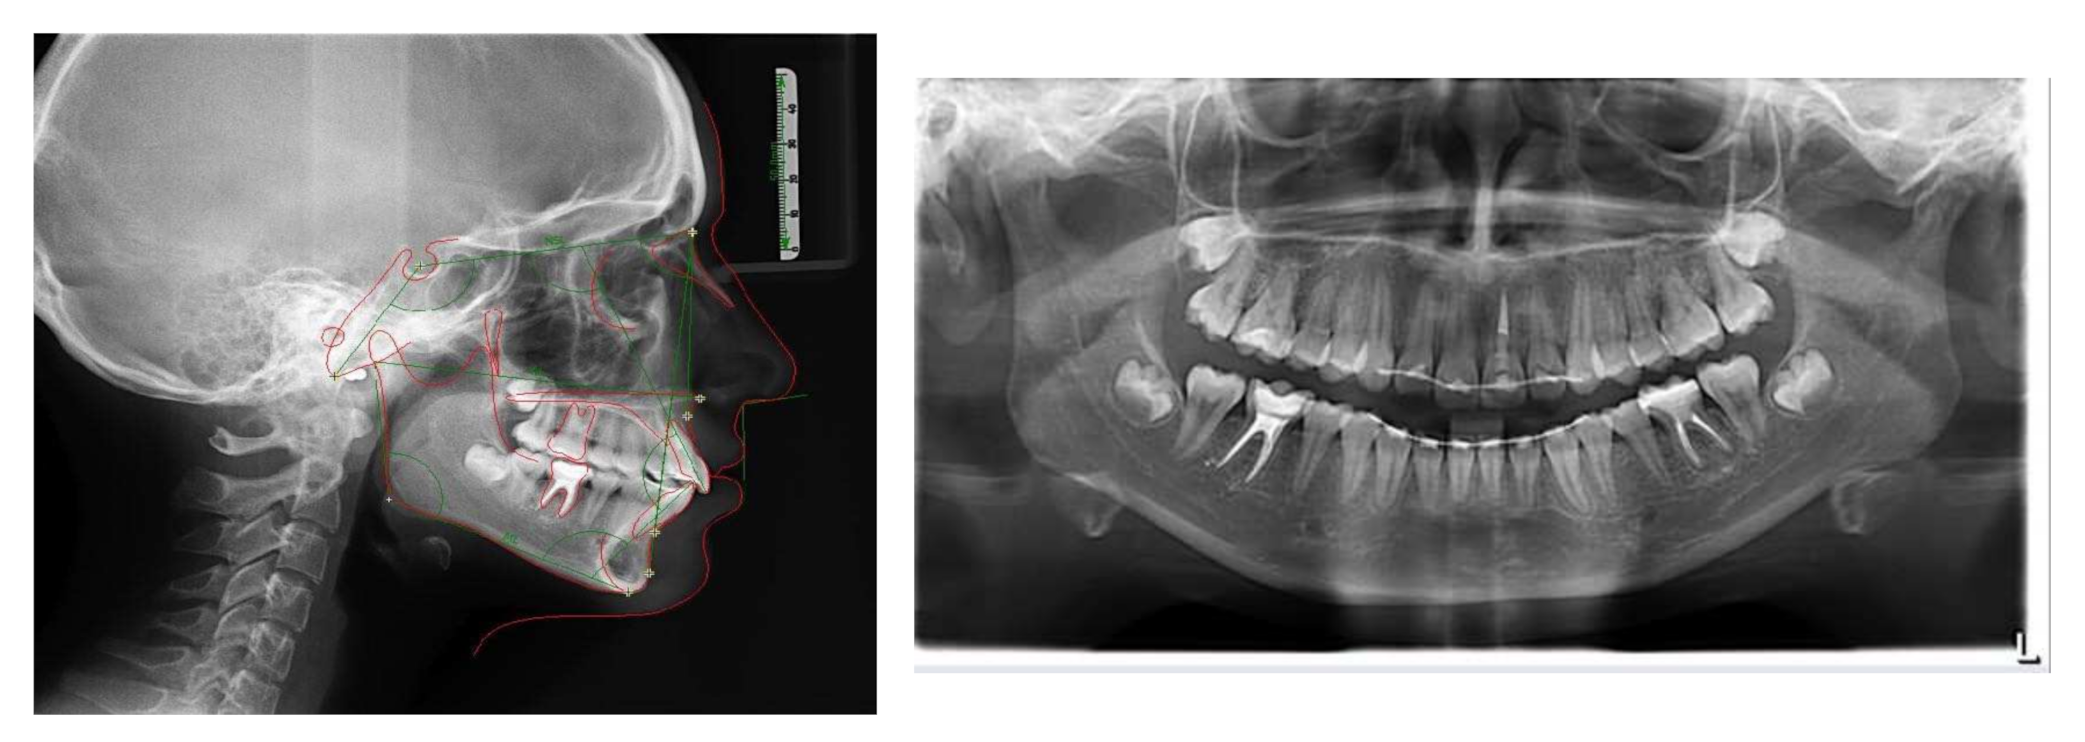

2. Diagnosis and Etiology